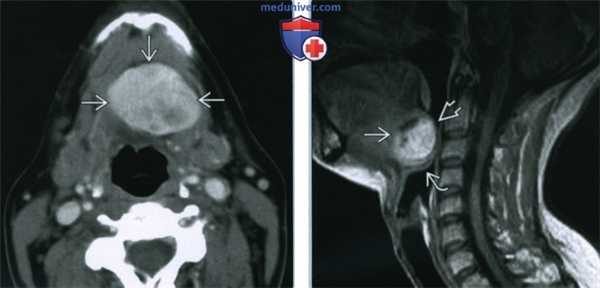

(Слева) На аксиальной КТ с КУ в области дна по средней линии определяется объемное образование с четкими контурами, представленное эктопической тканью щитовидной железы неоднородной плотности (может быть сопоставимо с ранними изменениями при зобе).

(Справа) На сагиттальной MPT (STIR, срединный срез) в основании языка визуализируется объемное образование с неоднородным гиперинтенсивным сигналом, заполняющее валлекулу. В этом случае язычная щитовидная железа обусловливает значительное сужение просвета ротоглотки, смещая надгортанник кзади и книзу.